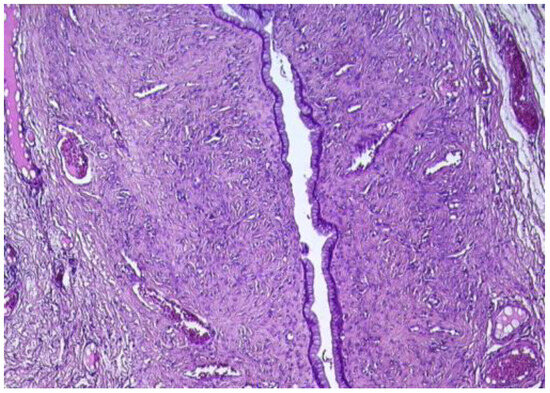

The histopathological microscopic assessment of the first structure revealed a cyst wall lined by a ciliated tubal-type epithelium (Figure 5), with endosalpingeal focal papillary projections.

Figure 5. Paratubal cyst lined by pseudostratified and simple columnar epithelium (HE ×20).